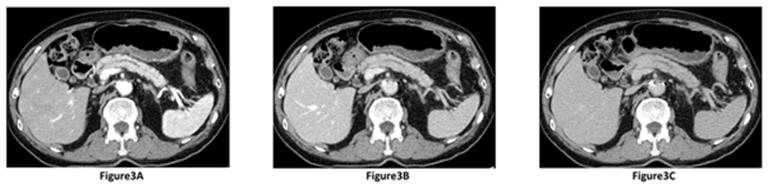

MRCP was performed 15 months after the initial hospitalization, which revealed short narrowing of the MPD (length, 12 mm) and slight upstream MPD dilatation (diameter, 5 mm). Thus, narrowing of the MPD and upstream MPD dilation was greater compared to that 6 months previously (Figure 1C). Quadriphasic (precontrast, pancreatic, portal venous and delayed phases) CT was performed. During the pancreatic phase of the dynamic study, a lesion of approximately 1 cm in diameter appeared hypoattenuating compare to normal adjacent pancreatic parenchyma in the pancreatic body (Figure 3A). This lesion became more dense during successive phases of study, and appeared isoattenuating compare to normal adjacent pancreatic parenchyma in portal venous (Figure 3B) and delayed (Figure 3C) phases. The serum levels of CEA and CA19-9 were 3.8 U/mL and 13.6 U/mL, respectively. On ERP, progression of MPD narrowing to 20 mm was noted, but brush cytology examination still showed no malignancy. EUS revealed the presence of a low echoic mass, approximately 20 mm in diameter, in the lesion at the MPD narrowing site. Therefore, we performed endoscopic ultrasonography fine-needle aspiration (EUS- FNA) for the low echoic mass. Only lymphoplasmacytic infiltration was observed, but no malignancy was noted on histopathological examination.

Figure 3A-C: Dynamic study of contrast-enhanced CT after 15 months; A. Hypoattenuating lesion of approximately 1 cm in diameter appears in the pancreatic body during the pancreatic phase compare to normal adjacent pancreatic parenchyma; B. Lesion appears isoattenuating during the portal venous phase compare to normal adjacent pancreatic parenchyma; C.Lesion appears isoattenuating during the delayed phase compare to normal adjacent pancreatic parenchyma. |

We consider that CT finding after 15 months follow-up was crucial because this could be the initial focal lesion of AIP in the present report. In the present study, the focal lesion appeared hypoattenuating during the pancreatic phase, and isoattenuating compare to normal adjacent pancreatic parenchyma during both portal venous and delayed phases. Typical dynamic CT findings of AIP reveal hypoattenuating during the pancreatic phase, and hyperattenuating in both portal venous and delayed phases [8]. CT finding during the portal venous phase is useful in differentiating focal AIP from pancreatic adenocarcinoma. Focal AIP during the portal venous phase appear hyperattenuating at diagnosis, and this finding is different from the findings of pancreatic cancer which most frequently remains hypoattenuating during the portal venous phase. The present case did not appear hypoattenuating during the portal venous phase, and this CT finding did not suggest pancreatic cancer.